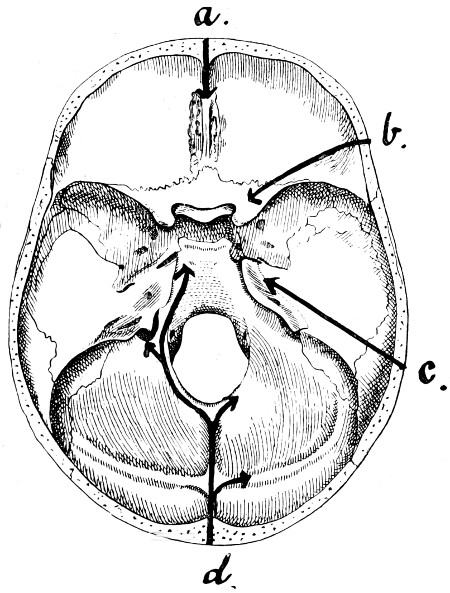

| 28. Illustrating the lines along which forces received on the vault are transmitted to the base | 69 |

| 29 A and B. The base of the skull and the base as seen on transillumination | 70, 71 |

| 30. Plan of the base of the skull | 77 |

| 31. To illustrate the relation of basic fractures to cranial nerves | 81 |

| 32-37. The lines pursued by basic fractures | 83-8 |